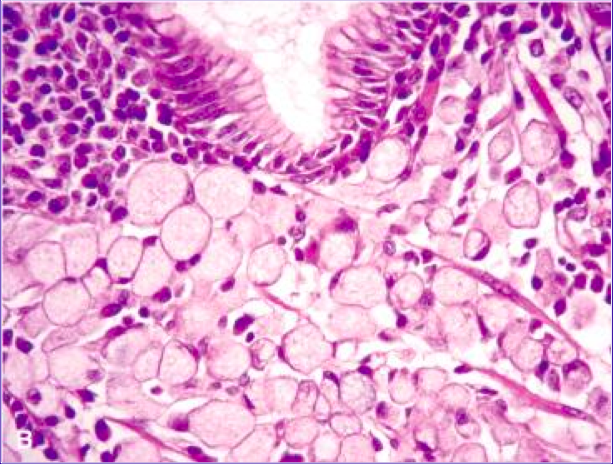

<p>What is meant by signet ring?</p>

<p>seen in diffuse gastric adenocarcinoma</p>

<ul>

<li>> 50% of the cells in tumor have large mucin vacuole w/ a flattened peripheral nucleus that looks ring-like (see image here)</li>

</ul>